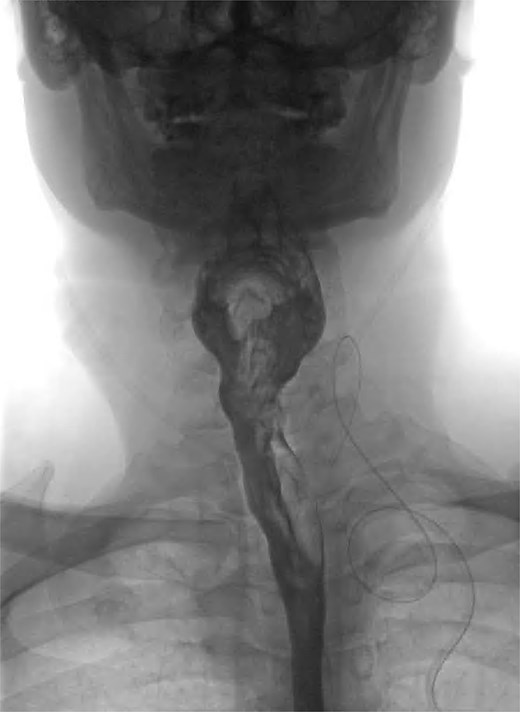

We present the case of a 57-year-old male patient who presented with dysphagia, regurgitation of undigested food, alongside a globus sensation. He had no significant medical history. He underwent a fluoroscopic swallow study, which revealed an anterolateral pharyngeal diverticulum consistent with a KJD with a neck of 5 mm and a length of 25 mm (Fig. 1). Given his symptoms, operative management was undertaken in which an incision was made along the medial border of the sternocleidomastoid. The platysma was divided, and dissection performed down to the level of the thyroid membrane with preservation of strap muscles. The left recurrent laryngeal nerve (RLN) was identified and preserved (Fig. 2). The esophageal diverticulum and sac were isolated from surrounding structures, and the neck was ligated using a 2/0 Vicryl prior to being excised. The ligation site was oversewn with 3/0 Vicryl. A drain was left, and the incision was closed in layers. Post-operatively, the patient underwent fluoroscopic swallow study, which did not show a leak or residual diverticulum, and after removal of the drain, the patient was discharged home day 1 postoperatively (Fig. 3).

Coronal view of postoperative fluoroscopic swallow study demonstrating no evidence of remnant diverticulum or leak.

Previous reports have highlighted the benefit of endoscopic treatments of ZD [3–5], as a minimally invasive approach. An endoscopic approach is, however, less favored in KJD due to its proximity to the RLN [6, 7] which enters the pharynx through the Killian-Jamieson space. As seen in Fig. 2, the RLN is visualized coursing close to the neck of the KJD. Open approach enables direct visualization of the nerve when compared to an endoscopic approach. Cricopharyngeal myotomy (CPM) is often recommended in the management of ZD, given cricopharyngeal muscle dysfunction playing a major role in its etiology. Due to its location below the cricopharyngeus, CPM is not considered to be central to definitive management of KJD [8].